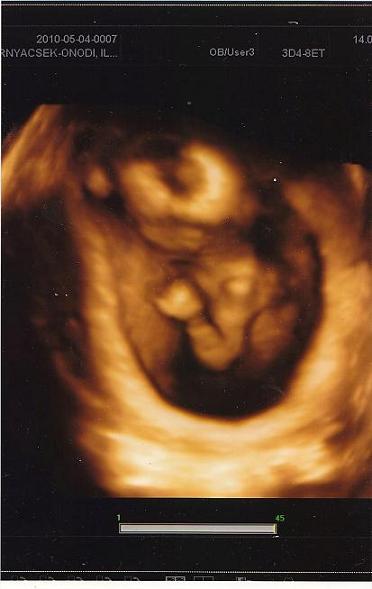

A vizsgálatok most nem tudom hogy vannak ott pontosan. Amikor Marcival voltam terhes, akkor a kórházzal egybeépített rendelőintézetbe kellett járnom uh-ra (sima uh volt ott akkor még), most meg a fehérvári úti sztkba járok, ahol 4d van. Nst-re is oda kellett járnom, ahova uh-ra, most nem tudom, hogy lesz.